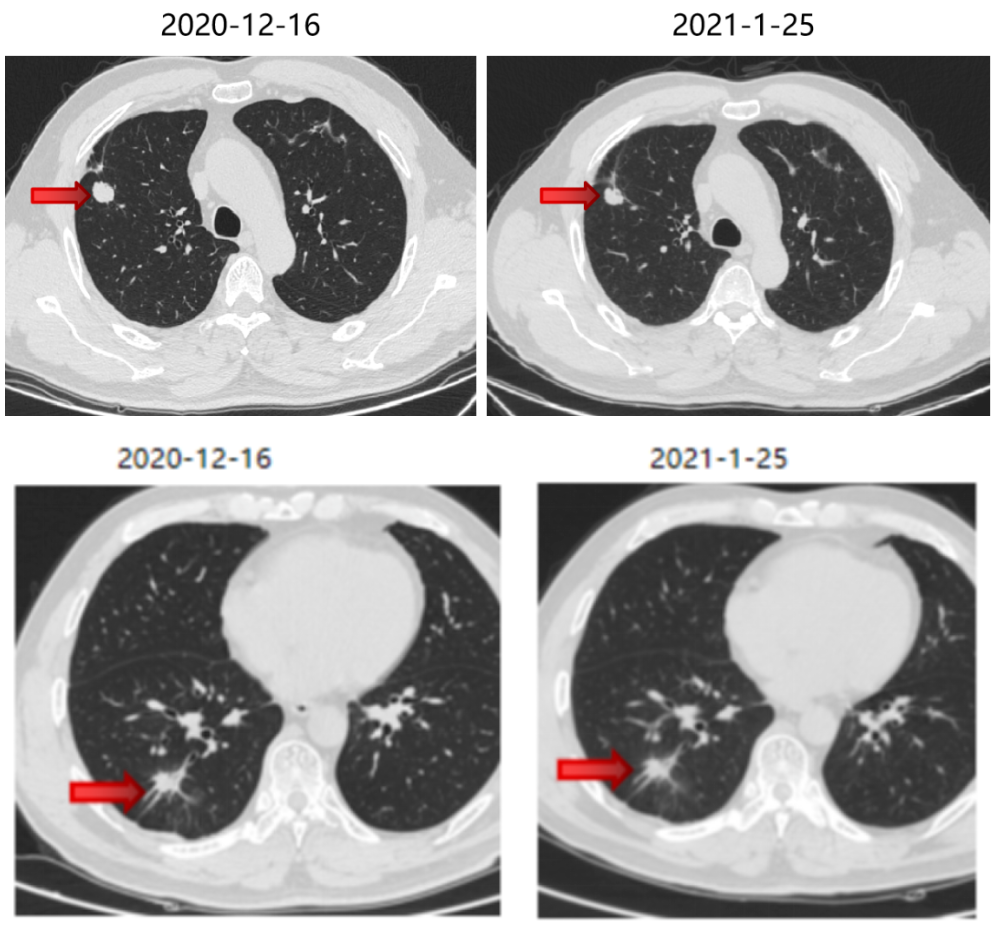

三线治疗

2021-1 起口服呋喹替尼3mg +曲妥珠单抗。

期间2021-3-15胸部CT:双肺转移瘤部分较前略增大,疗效SD。

三线治疗疗效评价:部分增大,PD。

四线治疗

2021-6-17 起口服曲氟尿苷替匹嘧啶片(TAS-102)40mg bid。

四线治疗疗效:部分略减小,SD。